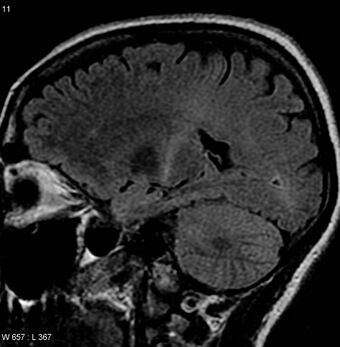

An MRI of the brain with increased T2 signal in the posterior part of the internal capsule that can be tracked to the motor cortex, consistent with the diagnosis of ALS

MRI (axial FLAIR) demonstrates increased T2 signal within the posterior part of the internal capsule, consistent with the diagnosis of ALS.

No test can provide a definite diagnosis of ALS, although the presence of upper and lower motor neuron signs in a single limb is strongly suggestive.[2] Instead, the diagnosis of ALS is primarily based on the symptoms and signs the physician observes in the person and a series of tests to rule out other diseases.[2] Physicians obtain the person's full medical history and usually conduct a neurologic examination at regular intervals to assess whether symptoms such as muscle weakness, atrophy of muscles, hyperreflexia, and spasticity are worsening.[2] A number of biomarkers are being studied for the condition, but so far are not in general medical use.[95][96]

Because symptoms of ALS can be similar to those of a wide variety of other, more treatable diseases or disorders, appropriate tests must be conducted to exclude the possibility of other conditions. One of these tests is electromyography (EMG), a special recording technique that detects electrical activity in muscles. Certain EMG findings can support the diagnosis of ALS. Another common test measures nerve conduction velocity (NCV). Specific abnormalities in the NCV results may suggest, for example, that the person has a form of peripheral neuropathy (damage to peripheral nerves) or myopathy (muscle disease) rather than ALS. While a magnetic resonance imaging (MRI) is often normal in people with early stage ALS, it can reveal evidence of other problems that may be causing the symptoms, such as a spinal cord tumor, multiple sclerosis, a herniated disc in the neck, syringomyelia, or cervical spondylosis.[2][100]